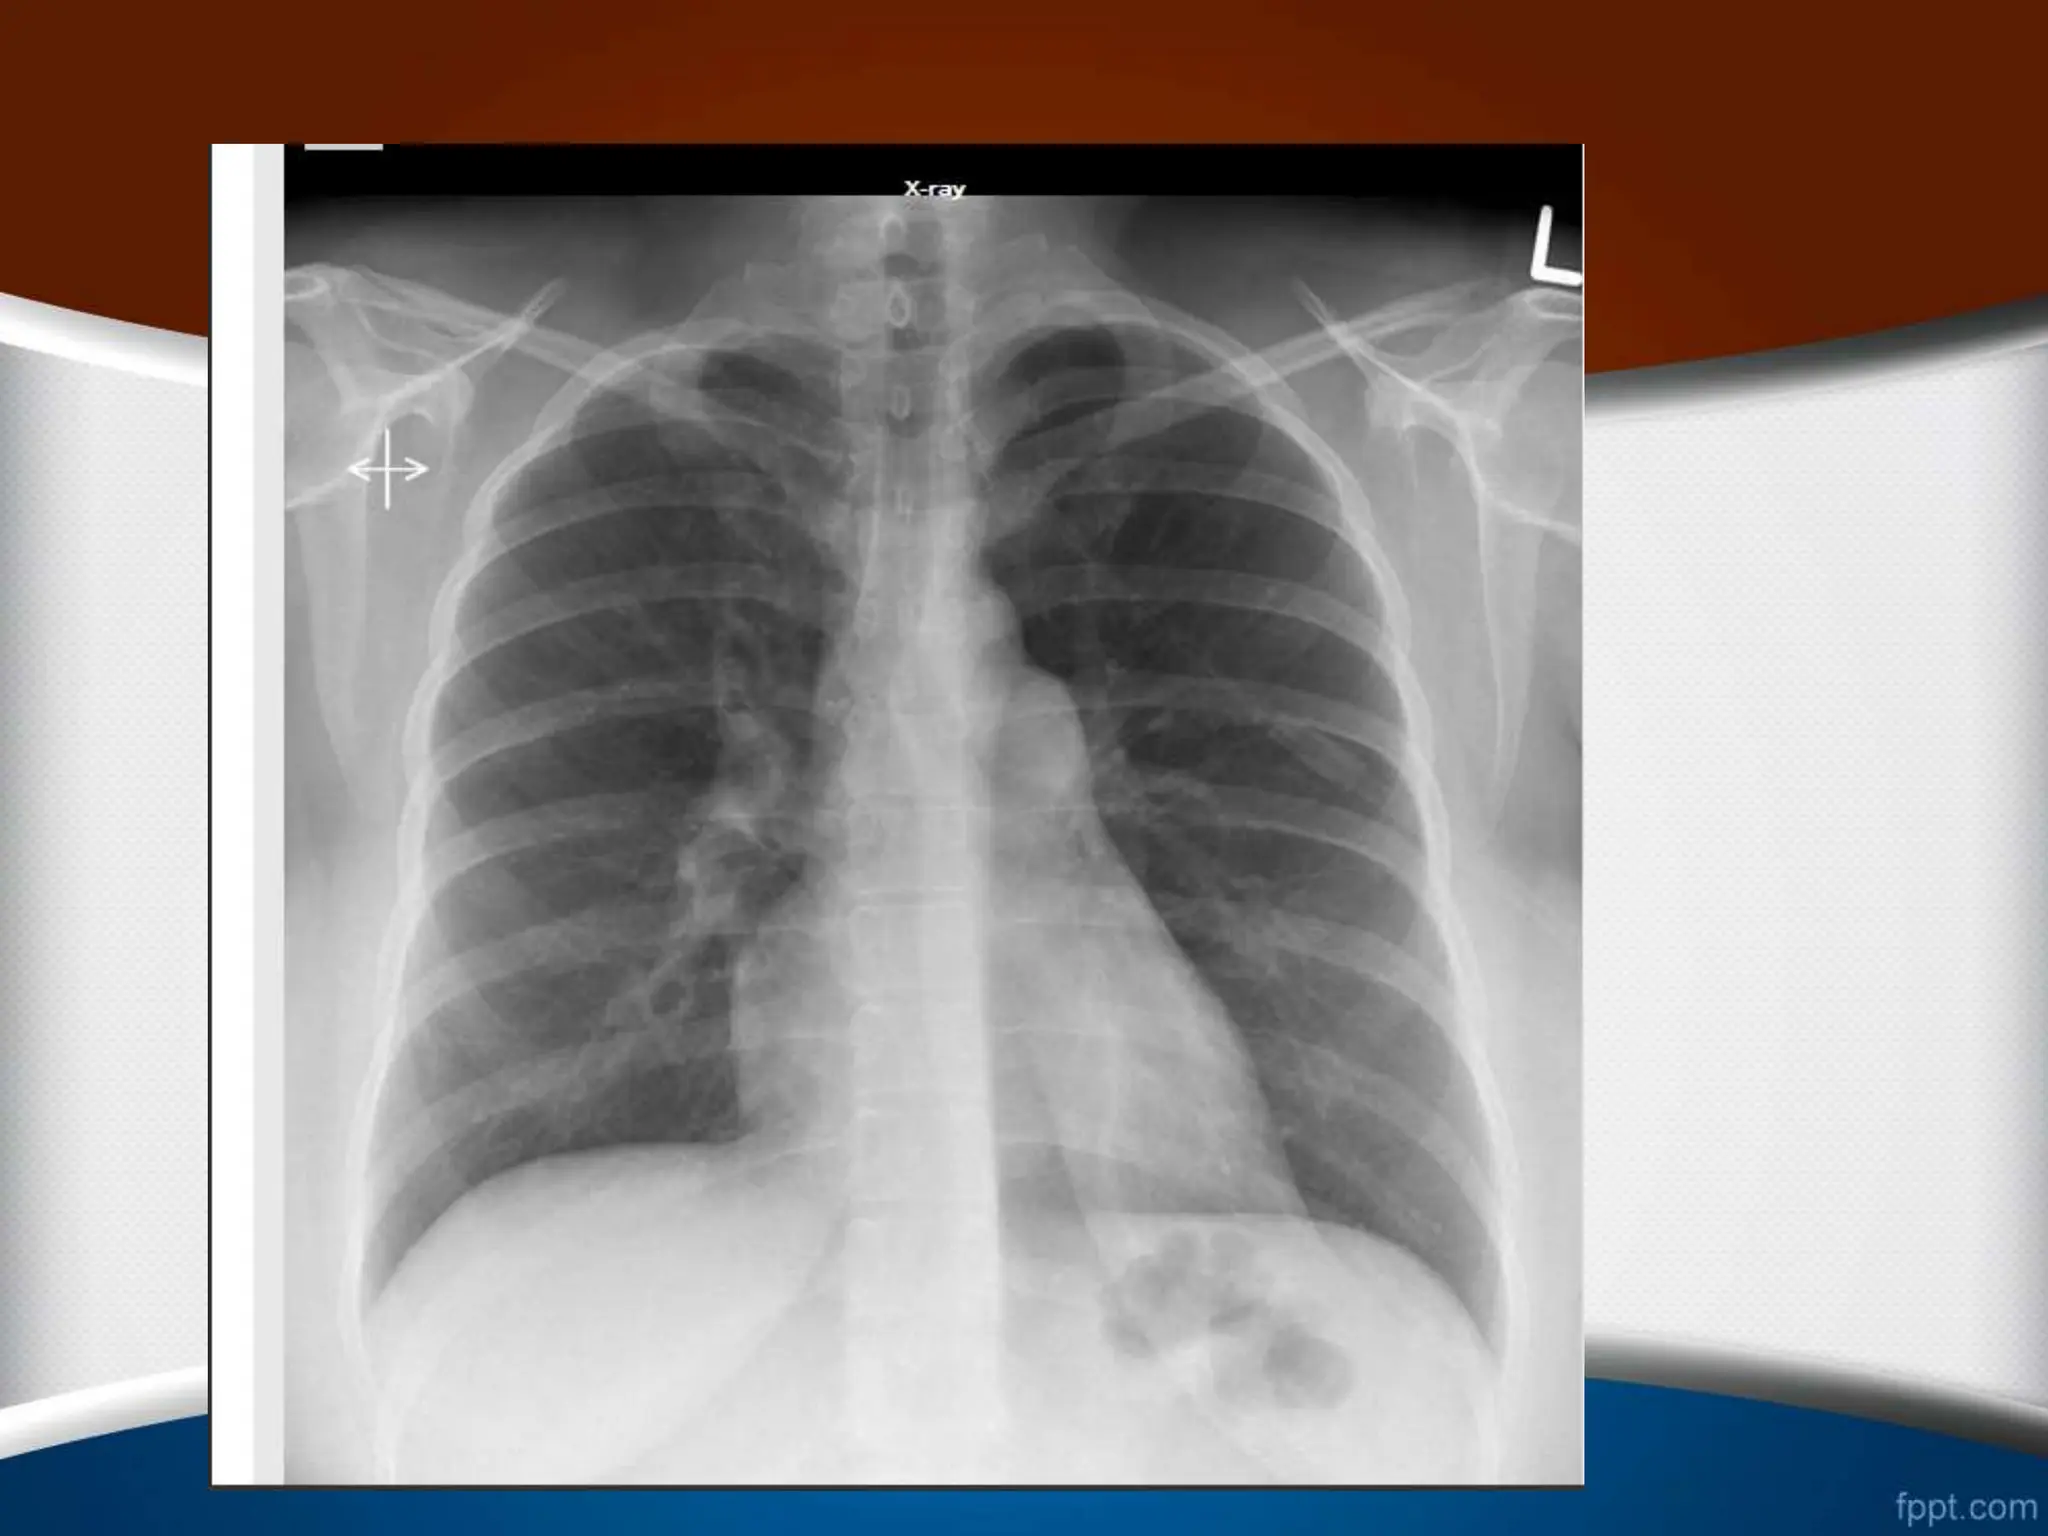

Exposure ‫قرار‬ ‫اشعه‬ ‫معرض‬ ‫در‬ ‫میزان‬ ‫یا‬

‫دنده‬ ‫و‬ ‫ریوی‬ ‫عروق‬ ،‫فقرات‬ ‫ستون‬ ‫مشاهده‬

‫نشان‬ ‫قلب‬ ‫پشت‬ ‫از‬ ‫ها‬

‫است‬ ‫اشعه‬ ‫میزان‬ ‫بودن‬ ‫مناسب‬

.

2

-

‫ریوی‬ ‫عروق‬ ‫اما‬ ،‫شود‬ ‫مشاهده‬ ‫فقرات‬ ‫ستون‬ ‫فقط‬ ‫که‬ ‫صورتی‬ ‫در‬

‫است‬ ‫تاریک‬ ‫فیلم‬ ‫نشود‬ ‫مشاهده‬

(Over exposure)

3

‫سفی‬ ‫خیلی‬ ‫فیلم‬ ،‫نشود‬ ‫مشاهده‬ ‫فقرات‬ ‫ستون‬ ‫که‬ ‫صورتی‬ ‫در‬

‫د‬

‫است‬

(Under exposure)

4

‫به‬ ‫را‬ ‫ها‬ ‫مهره‬ ‫بین‬ ‫فضای‬ ‫نباید‬ ‫مناسب‬ ‫اشعه‬ ‫میزان‬ ‫در‬

‫کرد‬ ‫مشاهده‬ ‫وضوح‬

5

‫تا‬ ‫ریه‬ ‫عروقی‬ ‫طرح‬

‫نزدیک‬

‫شود‬ ‫رؤیت‬ ‫ریه‬ ‫محیط‬ ‫به‬

exposure ‫مناسب‬